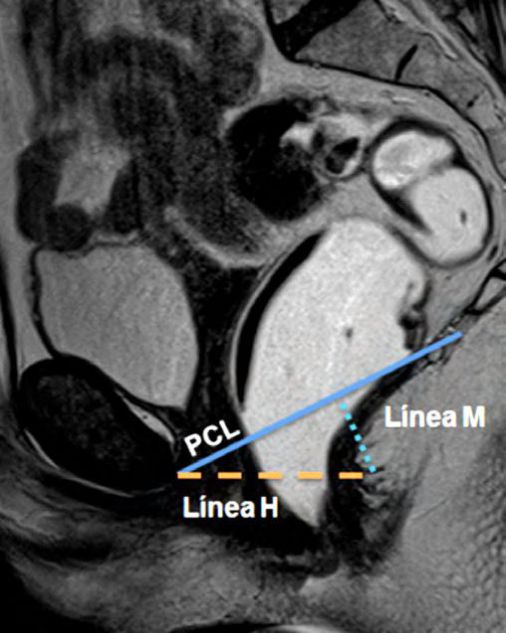

Figura 2

Líneas de referencia. Imagen de la línea media potenciada en T2 en el plano sagital, durante el reposo. Se trazaron la línea PCL (línea continua azul), línea H (línea punteada naranja) y línea M (línea punteada celeste). El músculo puborectal se topografía inmediatamente por detrás de la unión ano-rectal y el plano del elevador es paralelo a la línea PCL.

La línea H se traza desde el borde inferior del pubis hasta la pared posterior del recto a la altura de la unión ano rectal, representando el diámetro anteroposterior del hiato urogenital, con un valor normal menor a 6 cm (Ver figuras 4).

La línea M es perpendicular a la PCL a nivel del sector más posterior de la línea H y representa el descenso del hiato del elevador, con un valor normal menor a 2 cm. El ángulo ano rectal es el ángulo entre el eje central del canal anal y la pared posterior del recto, con un valor normal entre 108º y 127º y una variación de hasta 15º en Valsalva.